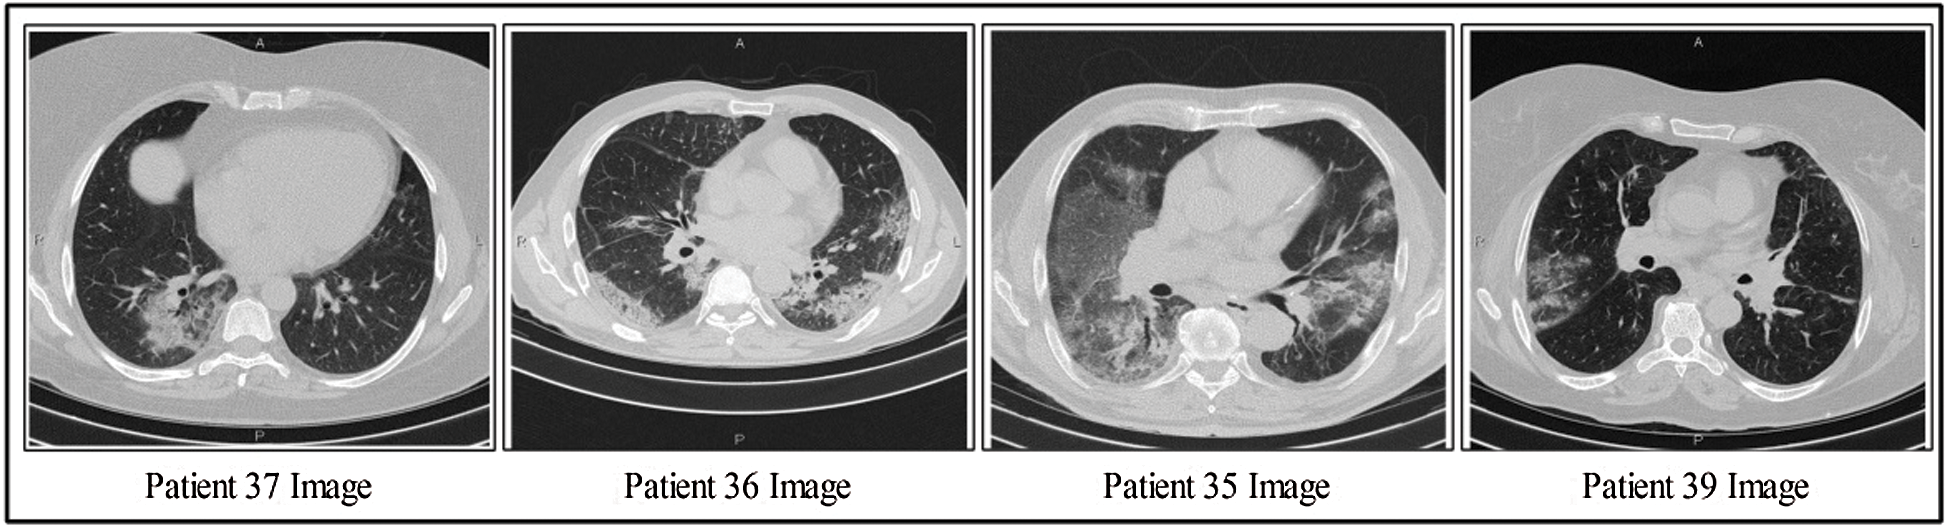

This section discusses the details of the self-created data set for evaluating the proposed scheme, as presented in Fig. 2. Data from 62 patients were collected from Radiopaedia (https://radiopaedia.org/articles/covid-19-4). This website contains data from 93 patients, of which the first 62 patients were selected for this work. Data from patients’ records included CT images, positive RT-PCR tests, travel history, and sex. The primary target of this research was to obtain information about positive COVID-19 scans. Also, 4,000 healthy CT images were obtained for classification. Several samples positive COVID-19 CT scans are shown in Fig. 2.

Figure 2: Few samples COVID-19 positive CT scans